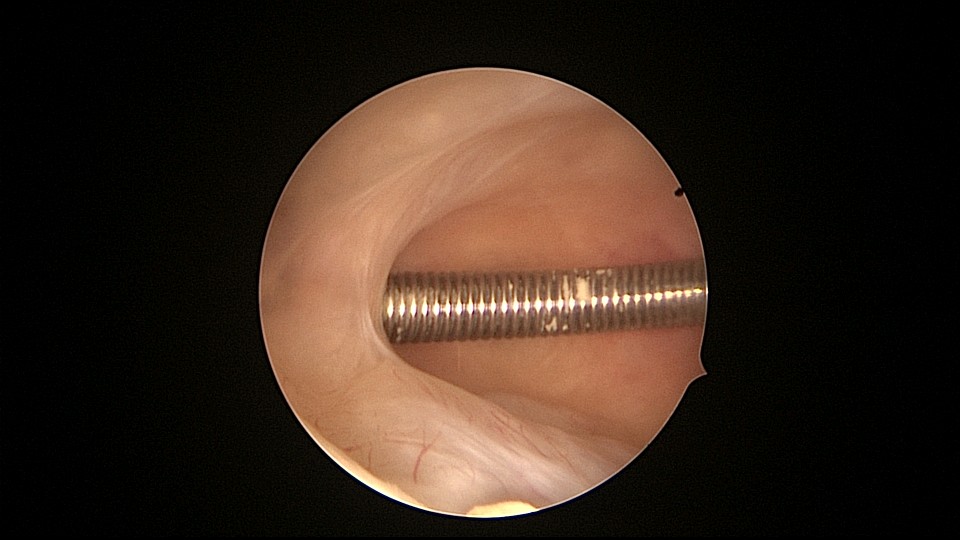

患者81岁,G5P5,顺产5次,安环50年,绝经23年,高血压病史多年,10年前因颅内肿瘤行开颅手术,4年前行腹腔镜胆囊切除术,外院介绍到我院宫腔镜取环。子宫前位,宫颈萎缩,穹隆展平,宫颈外口位于穹隆偏左侧,平滑狭小,夹持宫颈很困难,阴道内镜方式进入宫腔,见宫腔下部O型环圈内前后壁粘连,顿性分离粘连,宫腔中上部O型环与两侧宫壁嵌顿,异物钳松动节育环,但难以取出,取环钩沿镜鞘外侧进入宫腔,配合中弯钳牵拉出节育环,环变形,检查环完整,宫腔无其他异常。